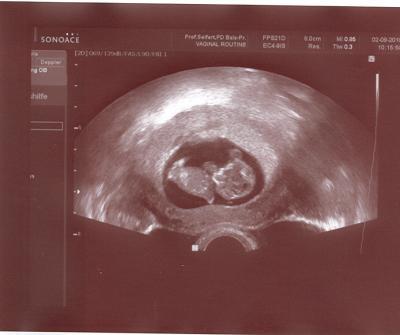

Hallo Mädels, hier das versprochene Foto von unserem Krümel!!! LG Bine